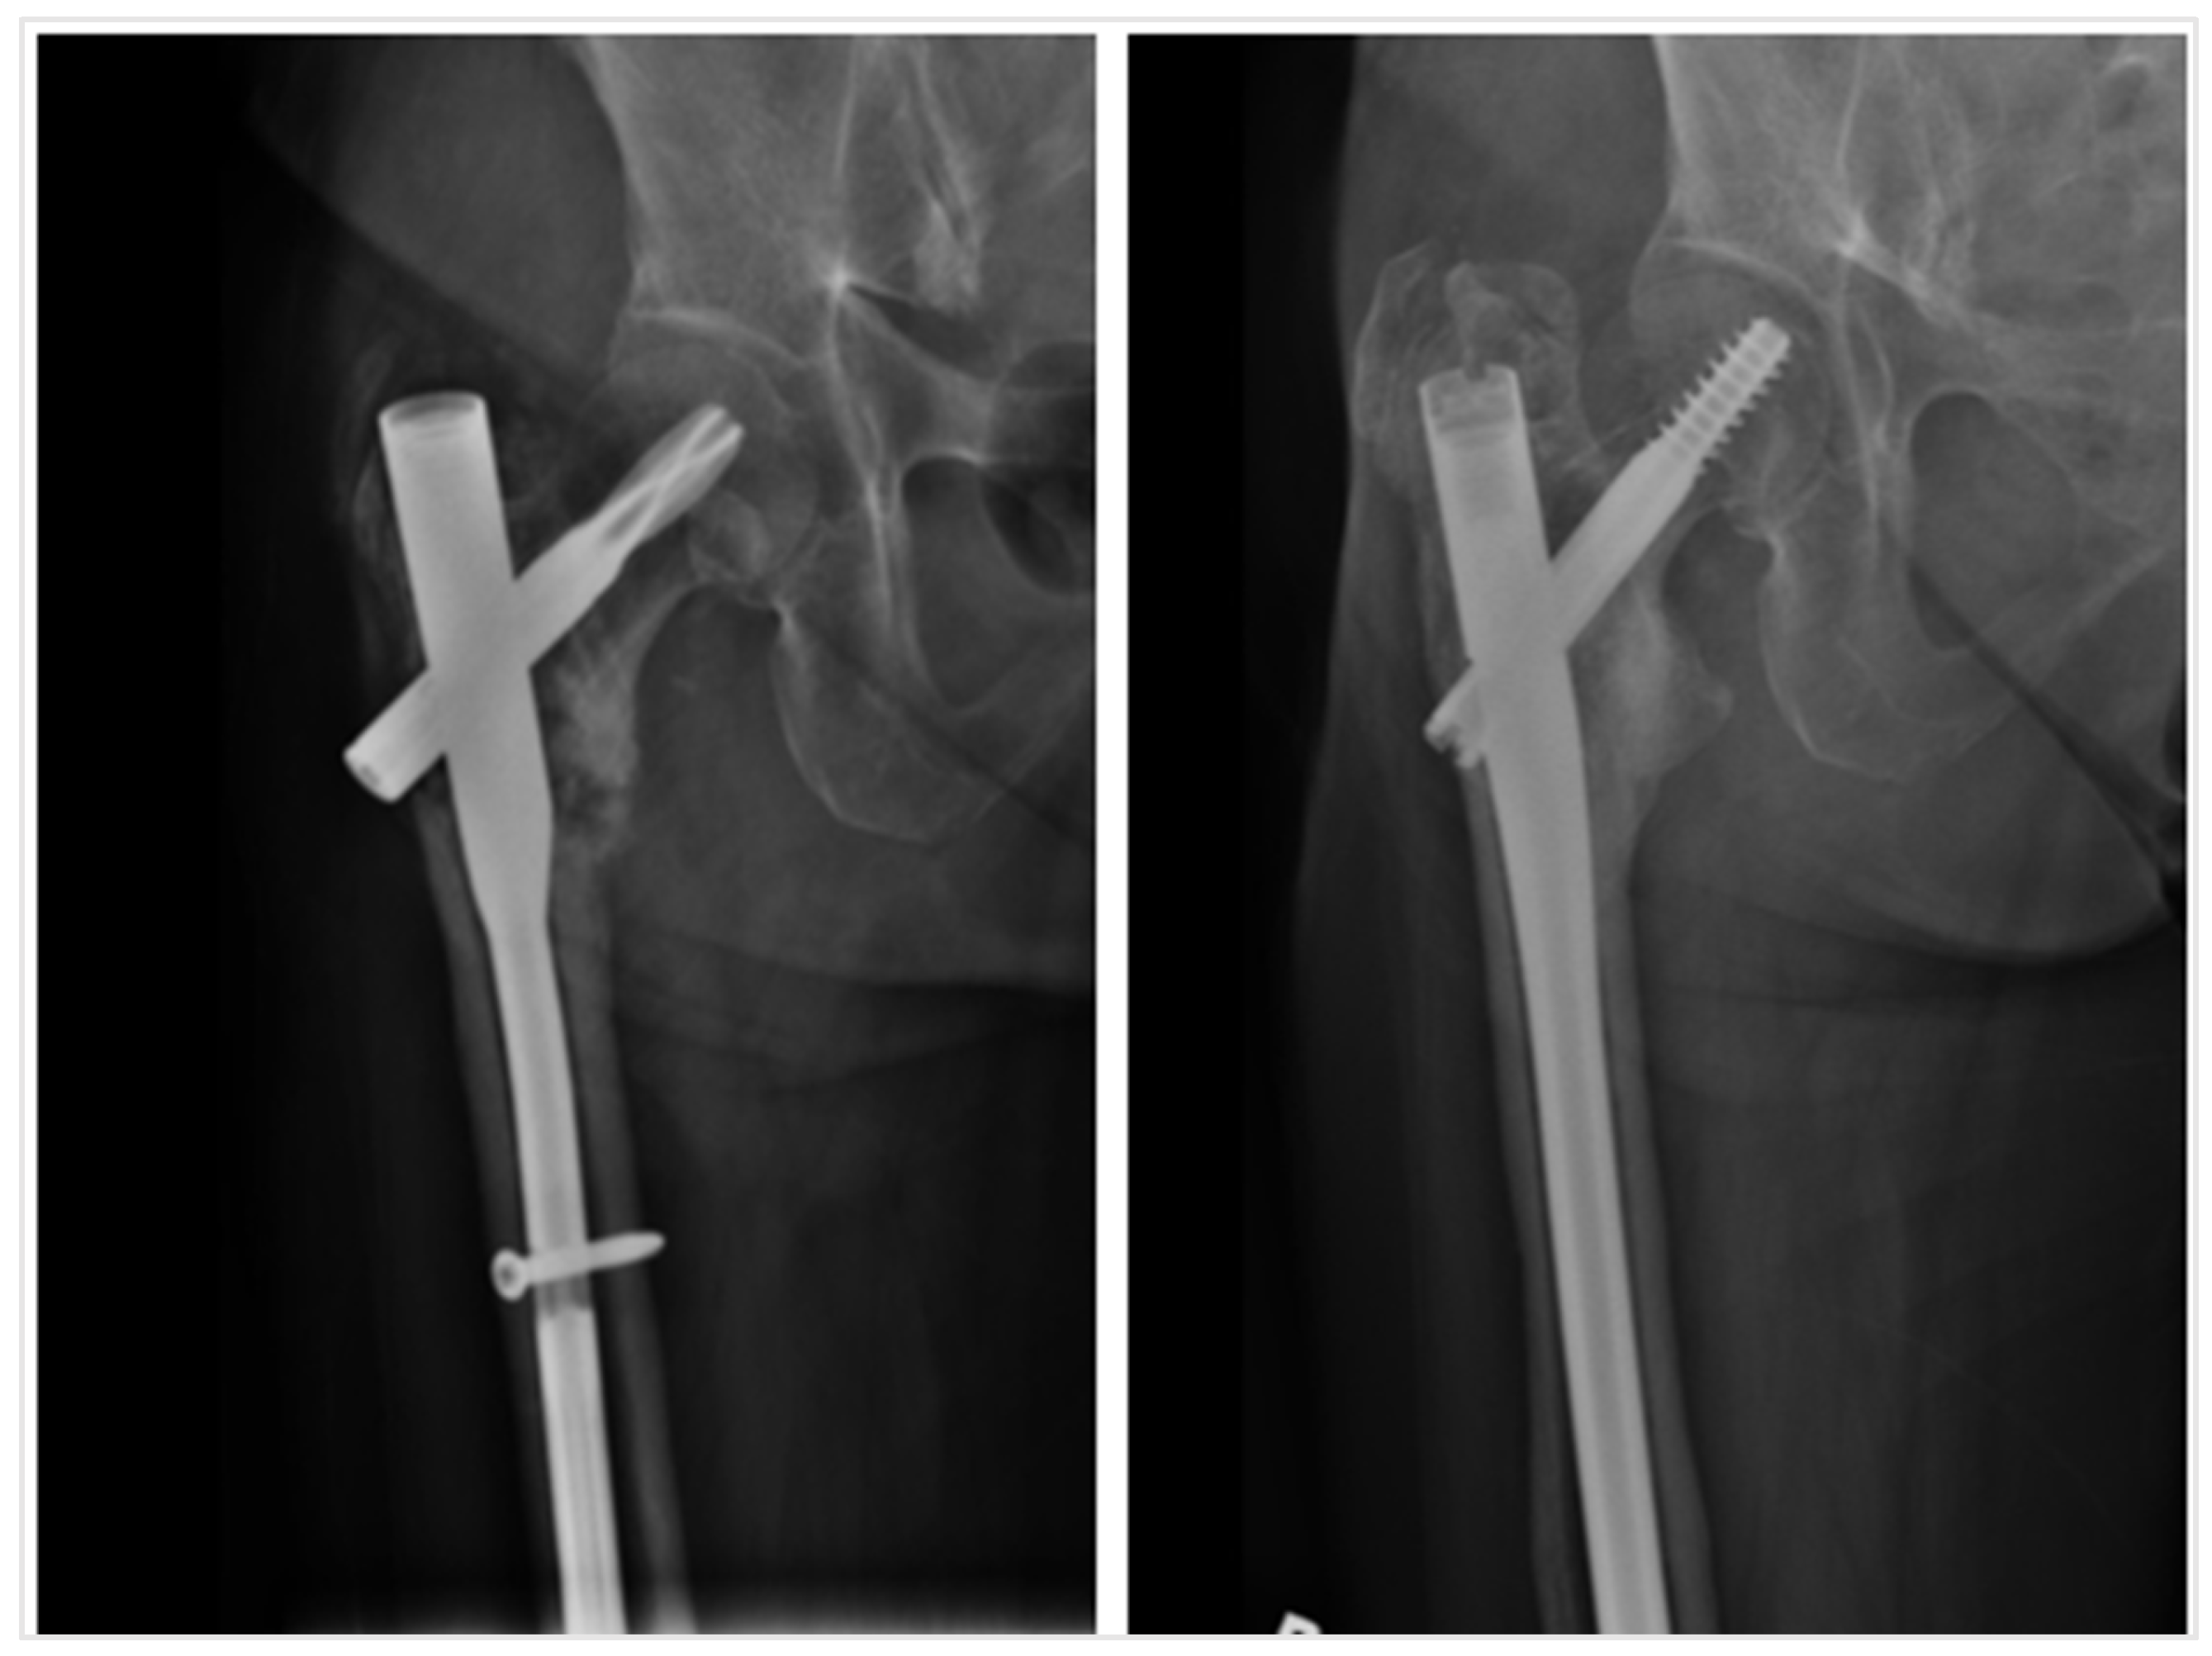

| Long cephalomedullary device | 51 (98.1%) | 1 (1.9%) | 52 |

| Short cephalomedullary device | 14 (87.5%) | 2 (12.5%) | 16 |

| Plate with screws | 0 (0%) | 1 (100%) | 1 |

| Total | 65 (94.2%) | 4 (5.8%) | 69 |